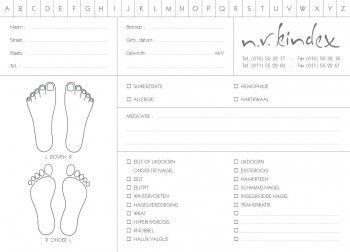

- manicure

- pedicurie (2)